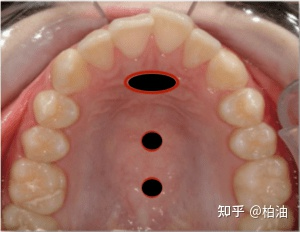

标准位置:前侧的椭圆是高舌位中舌尖的位置,之后的舌体贴着上颚摆放(即下方的两个小圆黑点)